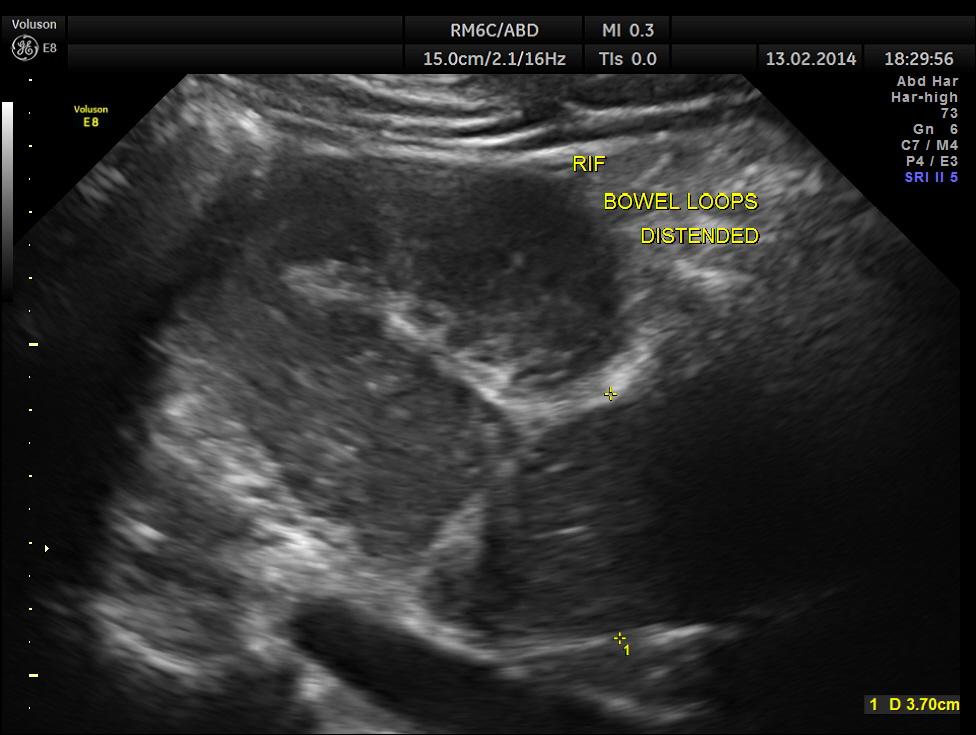

This was a 61 year old gentleman , who presented with complaints of acute abdominal distension , pain and history of constipation of 3 days duration . He showed the following findings :

grossly distended bowel loops

From his clinical presentation and the above findings , a diagnosis of intestinal obstruction was thought of and he was referred to a surgeon for further management.